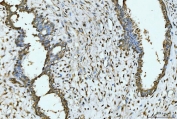

IHC staining of FFPE human liver cancer tissue with EXOSC8 antibody. HIER: boil tissue sections in pH8 EDTA for 20 min and allow to cool before testing.

IHC staining of FFPE human breast cancer tissue with EXOSC8 antibody. HIER: boil tissue sections in pH8 EDTA for 20 min and allow to cool before testing.

IHC staining of FFPE human appendiceal adenocarcinoma tissue with EXOSC8 antibody. HIER: boil tissue sections in pH8 EDTA for 20 min and allow to cool before testing.

IHC staining of FFPE human gall bladder adenosquamous carcinoma tissue with EXOSC8 antibody. HIER: boil tissue sections in pH8 EDTA for 20 min and allow to cool before testing.

IHC staining of FFPE human gastric adenocarcinoma tissue with EXOSC8 antibody. HIER: boil tissue sections in pH8 EDTA for 20 min and allow to cool before testing.

IHC staining of FFPE human renal clear cell carcinoma tissue with EXOSC8 antibody. HIER: boil tissue sections in pH8 EDTA for 20 min and allow to cool before testing.

IHC staining of FFPE human lung cancer tissue with EXOSC8 antibody. HIER: boil tissue sections in pH8 EDTA for 20 min and allow to cool before testing.